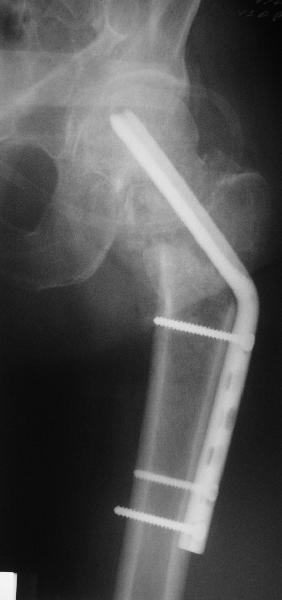

Нелеченный перелом шейки бедра

Поступил пациент 50 лет, из области. Травма 18.08.08. Лечили консервативно.

Сейчас вот чего-то спохватились и направили. Движения в тазобедренном суставе практически безболезненны, кроме форсированной внутренней ротации. В остальном проблем со здоровьем нет.Рентгенограмма в приложении. Видимо, выбирать приходится в первую очередь между вальгизирующей остеотомией и эндопротезированием.

Dear All,A male 50 years old referred to our institution from a rural hospital. Injured Aug 18. Managed nonoperatively. Hip motions are pain free except forced internal rotation. No other comorbidities.Images attached. Looks like main options are valgus osteotomy or THA. What would be optimal? Any other ideas? THX!

Приветствую всех. Спасибо за активное участие в обсуждении. Выбрали вариант с остеотомией.

Снимки в приложении.